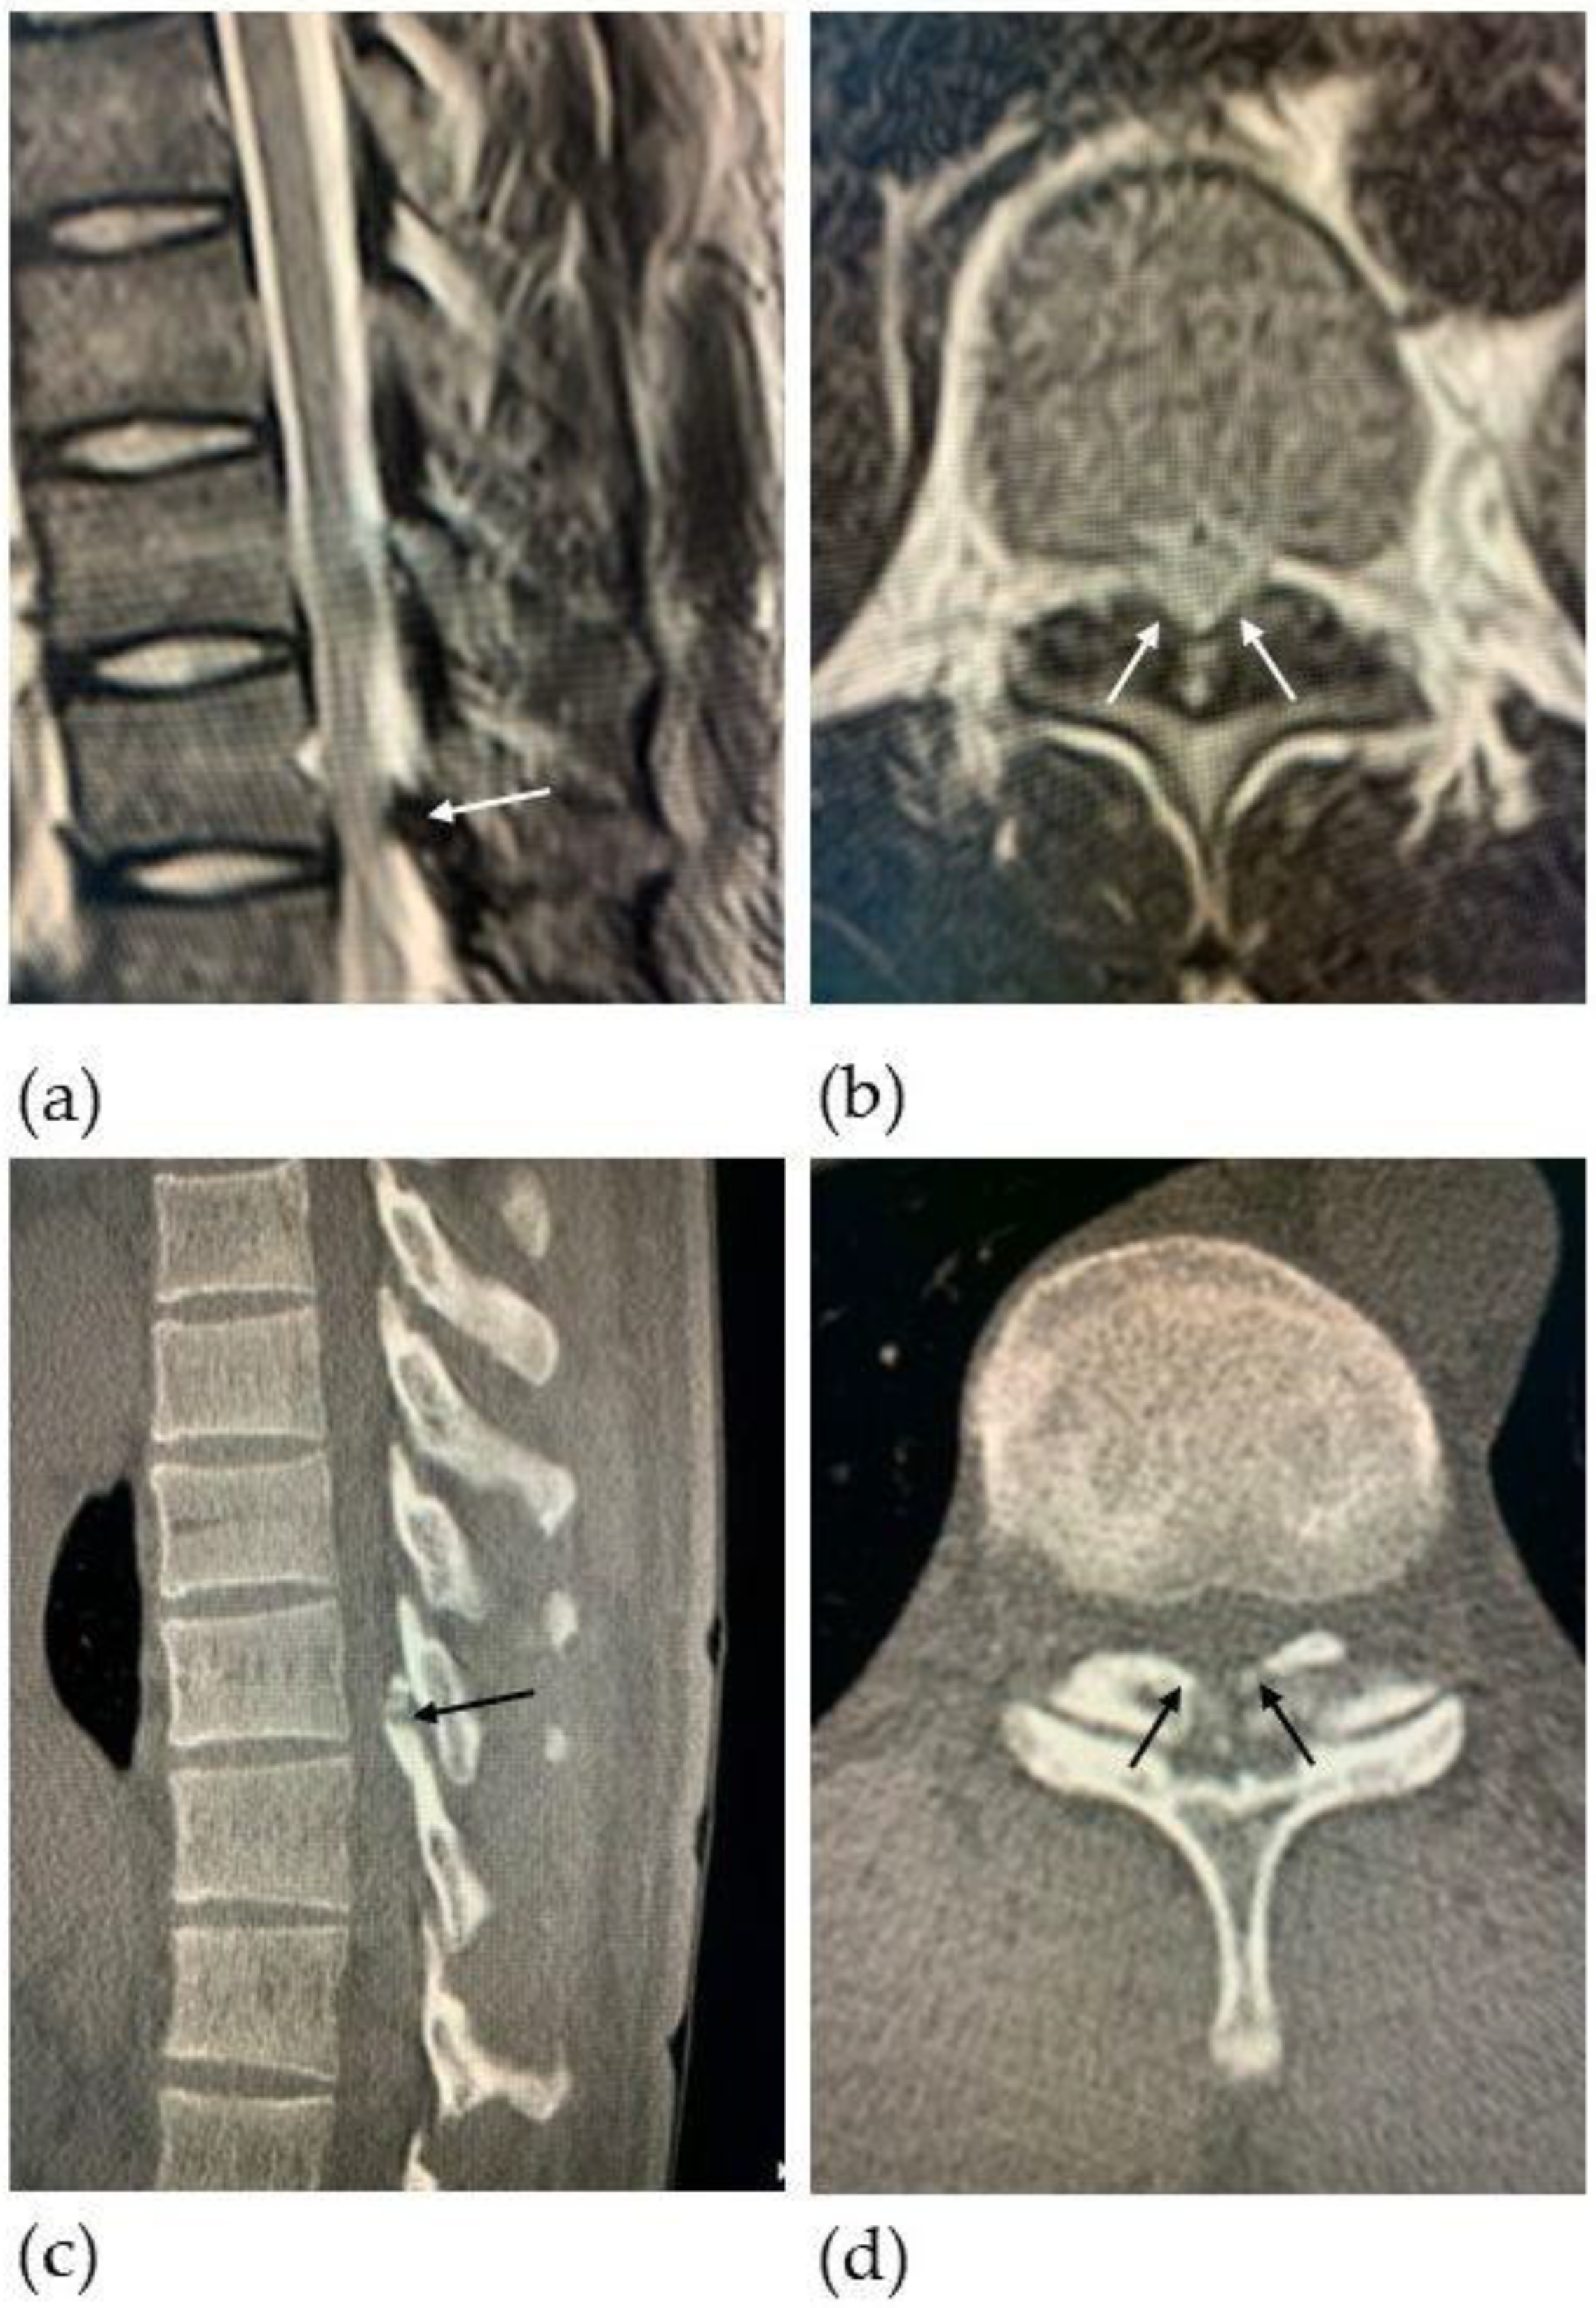

2.1. Patient Presentation

2.2. Surgical Technique